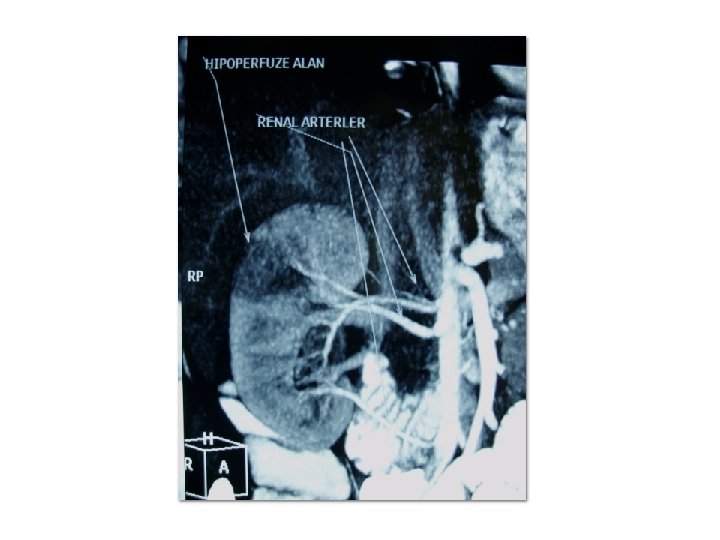

ATEROSKLEROZ SONUÇLARI • En yaygın görülen süreç, olarak adlandırılan yumuşak plakların yırtılmasıdır. Bunun sonucunda oluşan kan pıhtısı, kanı 5 dakika gibi kısa bir sürede yavaşlatır veya durdurur ve ölüme yol açabilir. Bu olaya enfarktüs denir. Bunun en yaygın senaryosu kalp krizidir, yani trombozun bir koroner arterin içinde meydana geldiği miyokardiyal enfarktüstür. İlerlemiş aterosklerozda görülen başka bir yaygın senaryo ise klodikasyon olarak adlandırılır, bu durumda stenoz ve anevrizmanın birleşimi sonucu bacaklara yeterli kan gitmez ve bunun sonucu hasta topallar. Böbrek, barsak ve diğer organlardaki arterler de aterosklerozdan etkilenebilir.